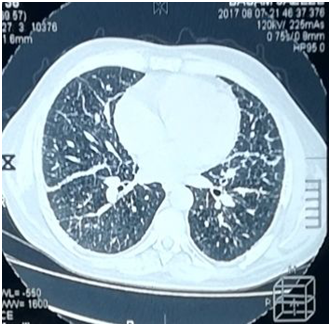

The patient's labs level was within normal except for CRP was elevated. By three separated measurement (one hour between each), water deprivation test revealed increased serum osmolality, increased serum Na+ and decreased urine osmolality. Hormonal Laboratory tests showed decreased FT4 and Testosterone. Magnet Resonance Imaging of pituitary gland was normal and no abnormality was detected (Figure 1). Chest X-ray showed diffuse interstitial reticular densities in both pulmonary fields (Figure 2). X-ray of pelvis and legs showed lytic lesions.

Pulmonary involvement is observed in 20-40% of LCH patients and can give symptoms, such as pneumothorax, dyspnea, tachypnea, and cough. Imaging studies of the lungs may reveal cysts and micronodular infiltrates.7 The patient had grade II dyspnea. CXR and MS- CT imaging of the lungs showed diffused interstitial reticular density. We performed Bronchoscopy and biopsy that showed histological features consistent with LCH.